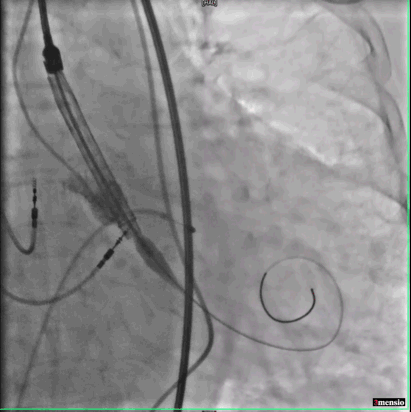

跨瓣